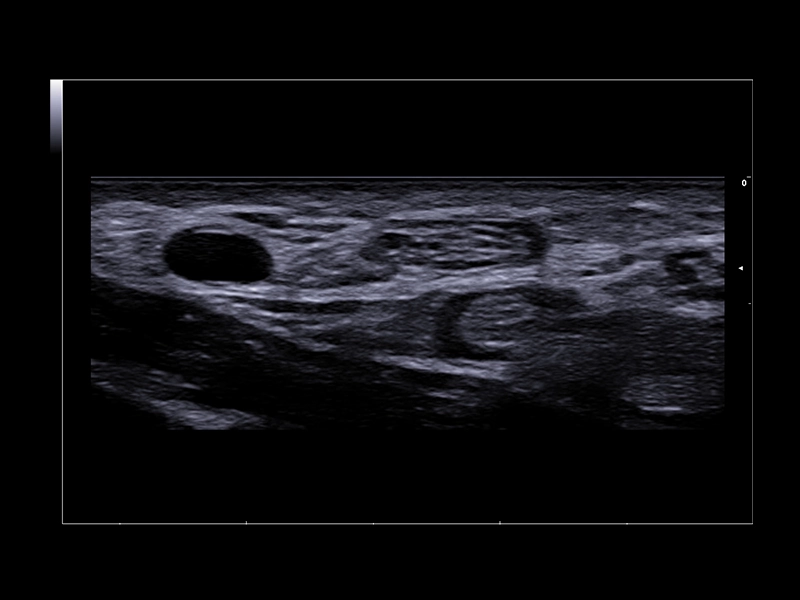

MyLab™9 Platform - High resolution imaging in testis

MyLab™9 Platform - High resolution imaging in testis